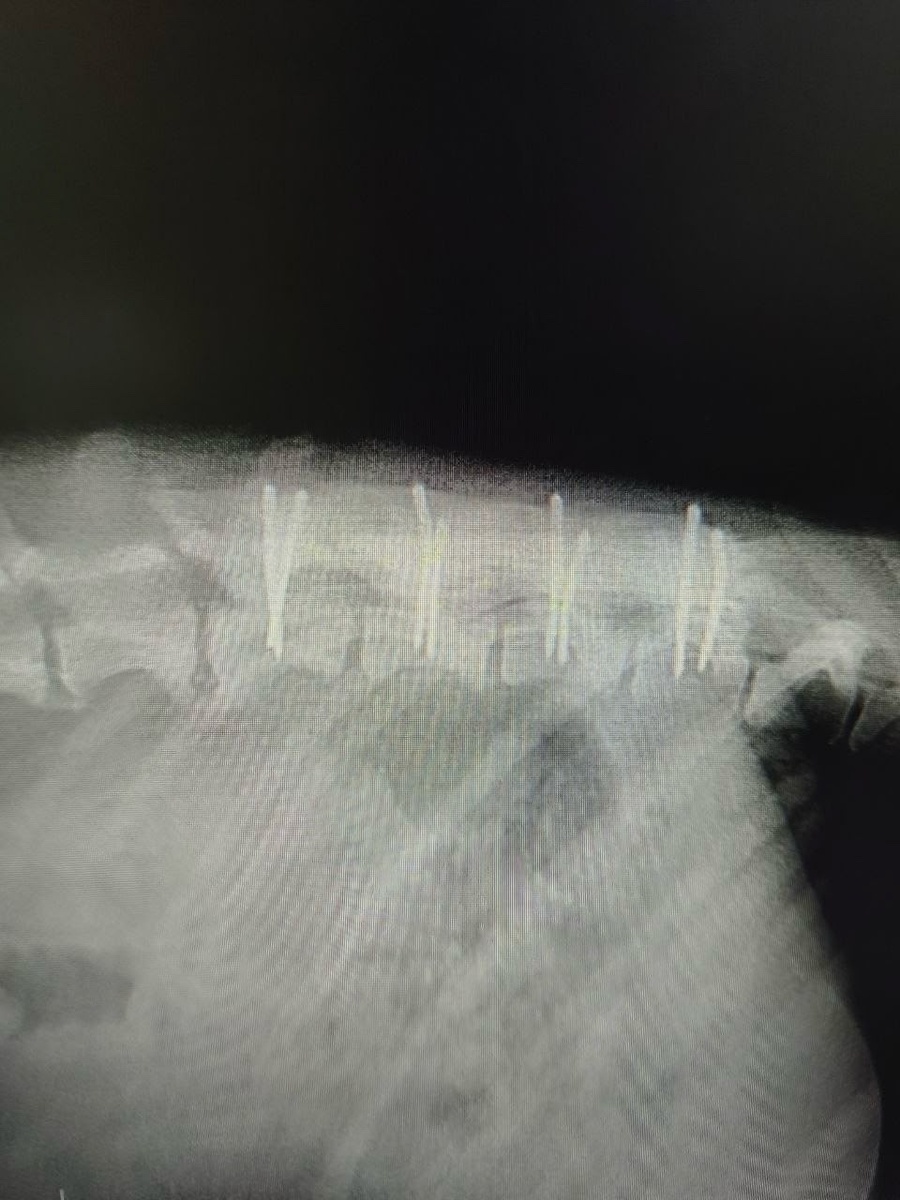

6 апреля у Карандаша отказали задние лапы, и Роман привёз его в Курскую ветклинику на консультацию. После осмотра невролога и КТ была проведена хирургическая стабилизация сегмента позвоночника.